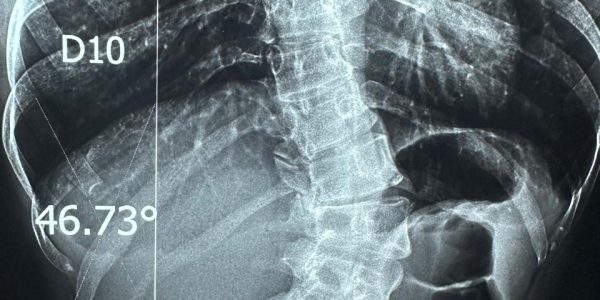

علاج اعوجاج شديد بالعمود الفقري

نجاح جراحة معقدة لتصحيح اعوجاج العمود الفقري بمستشفى قليوب التخصصي

نجاح جراحة معقدة لتصحيح اعوجاج العمود الفقري بمستشفى قليوب التخصصي   نجح الفريق الطبي بمستشفى قليوب التخصصي في تحقيق إنجاز طبي جديد، وذلك بعد تمكّنه من إجراء عملية دقيقة لمريضة كانت تعاني من اعوجاج شديد بالعمود الفقري، حيث تم إصلاح…